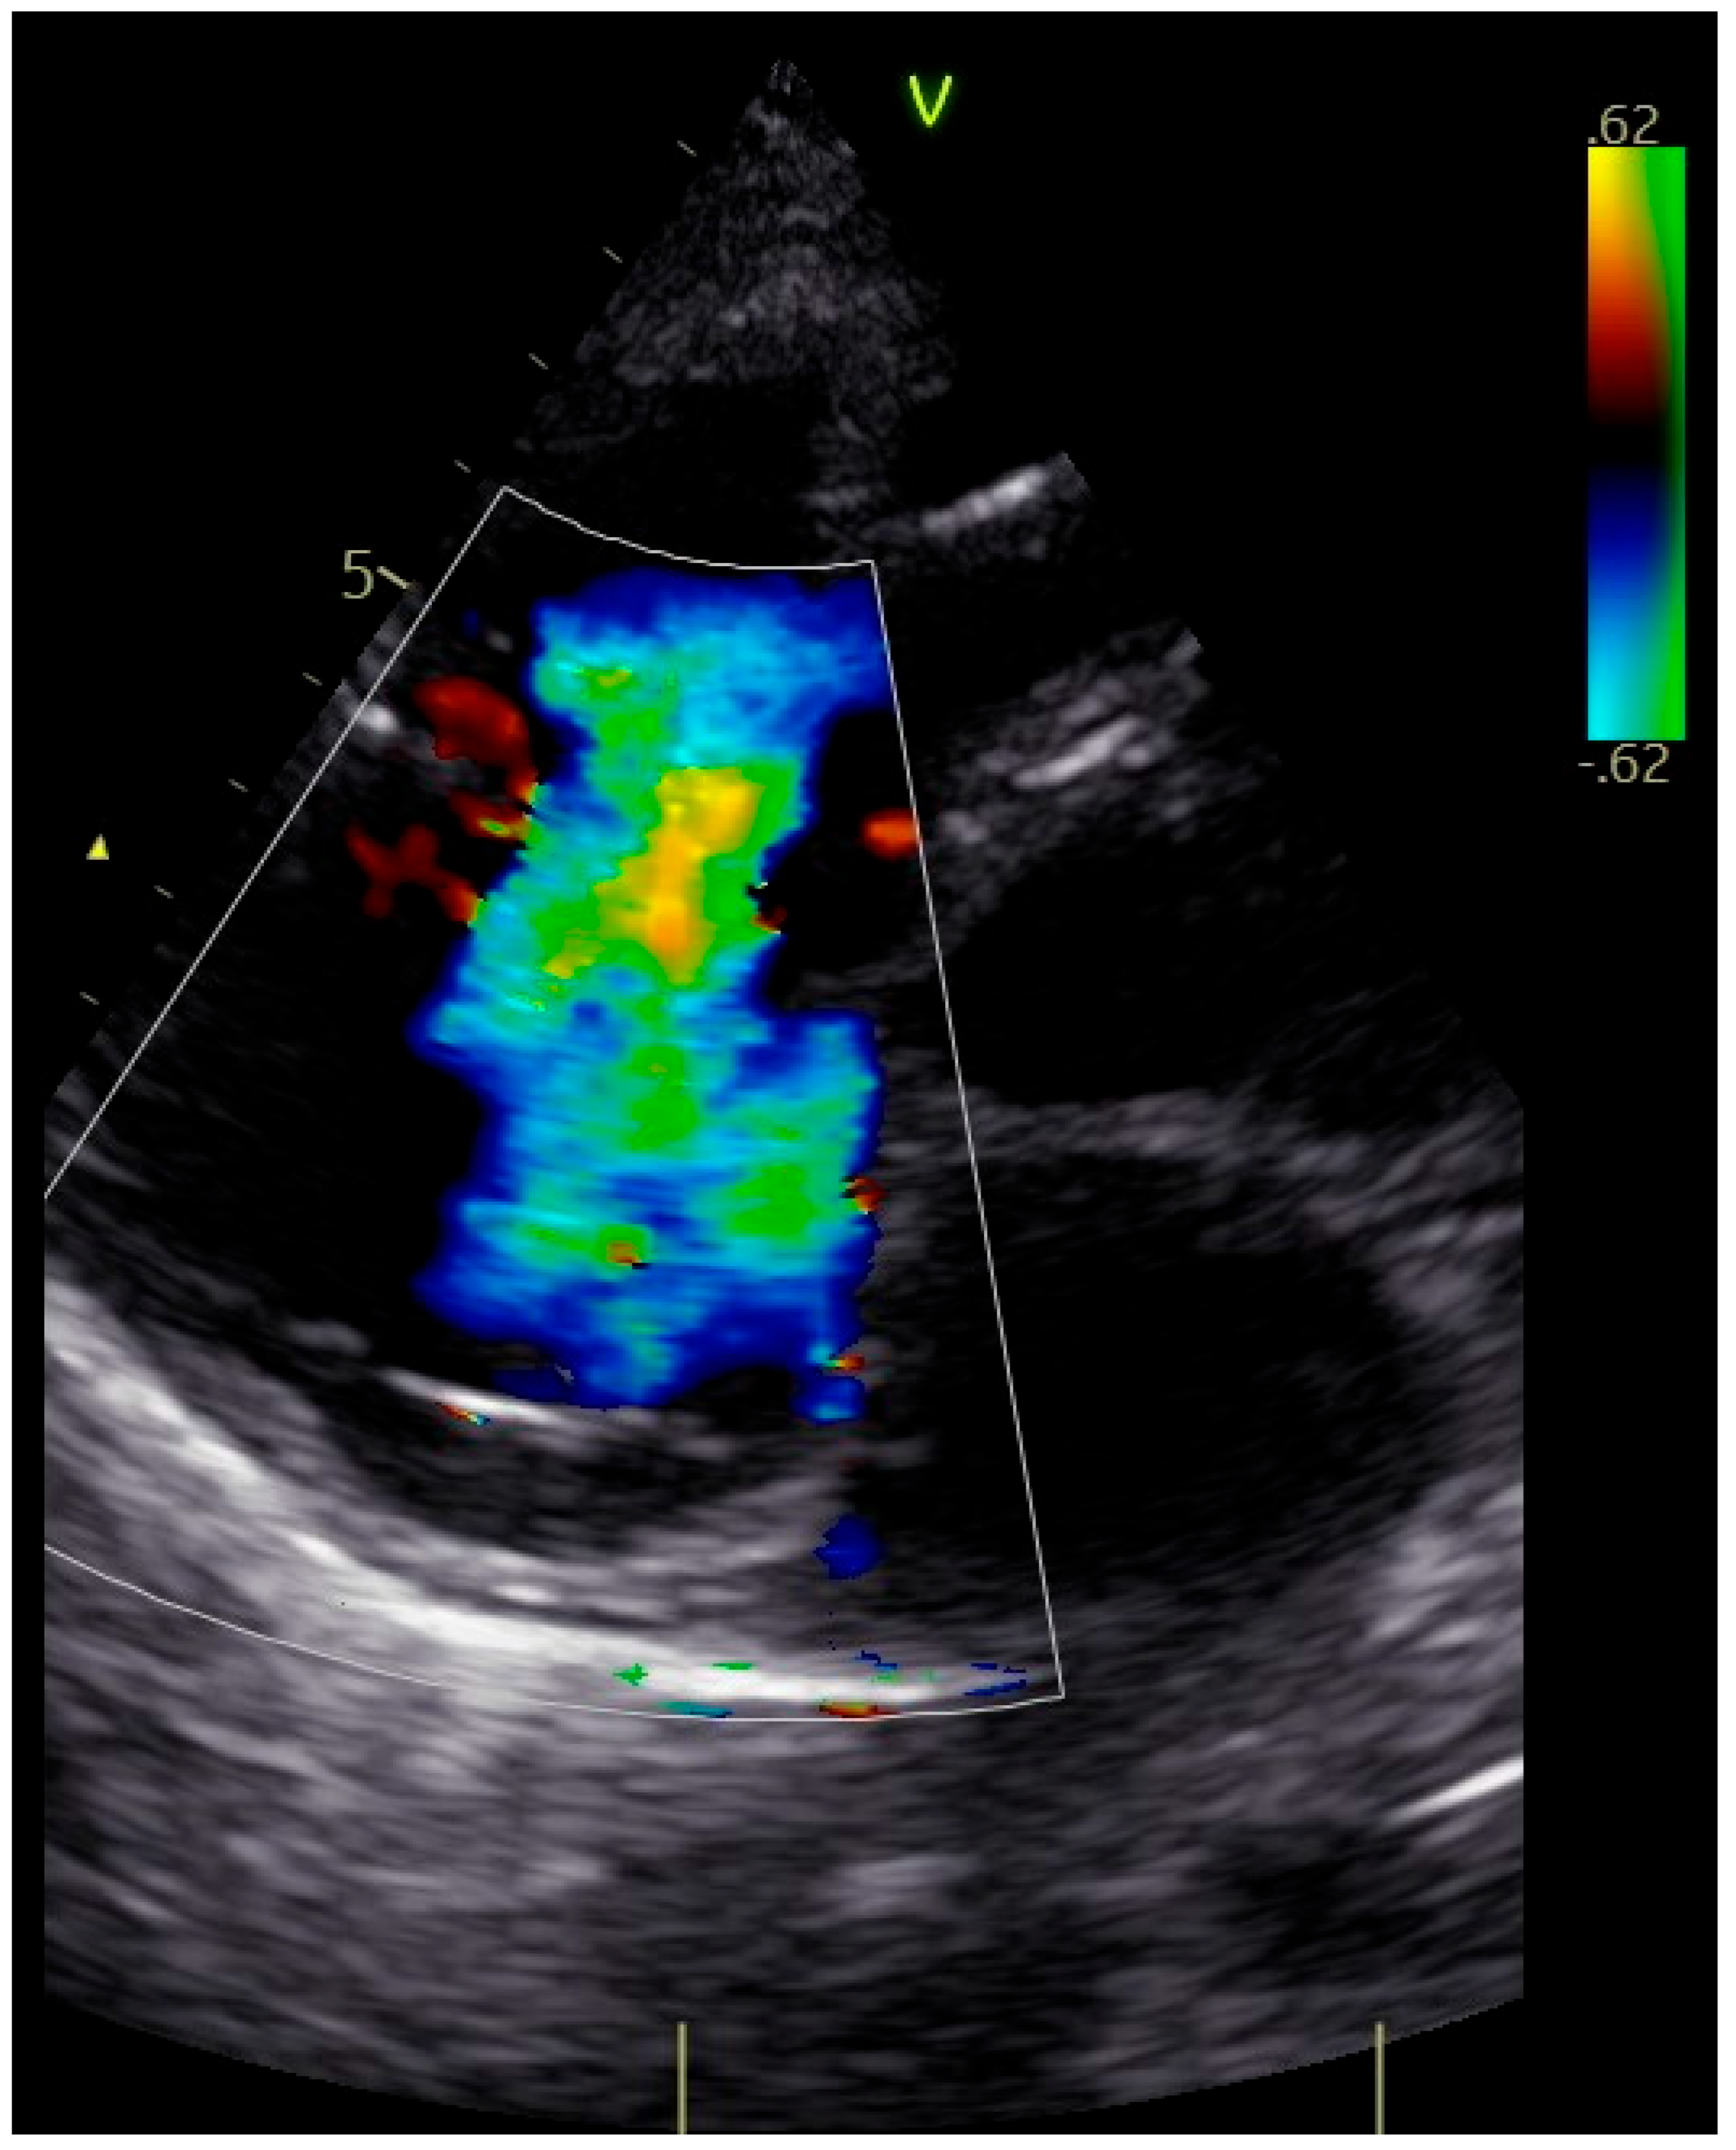

The patient was transferred to our hospital due to another exacerbation of HF. Echocardiography revealed severe tricuspid valve regurgitation (TR) (Figure 2). The tricuspid valve septal cusp was in a restricting position due to the two ventricular leads passing through the valve. The tricuspid valve leaflets had no coaptation. The right ventricle’s function was normal (Figure 3). After radiation therapy, increased scarring was found on the chest skin (Figure 4). One year ago, the patient underwent skin grafts due to healing wounds on her chest. The remaining right ventricle and atrium leads were transvenously removed. However, the procedure did not reduce tricuspid regurgitation (Figure 5).

Figure 2. Four-dimensional echocardiographic image—severe functional tricuspid regurgitation (arrow).